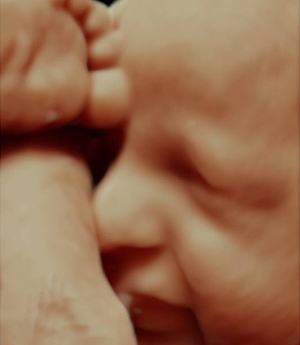

Com a inovação da medicina diagnóstica a ultrassonografia em 4D consegue avaliar a morfologia fetal em três dimensões em tempo real. As imagens tridimensionais permitem ver estruturas como as mãos, pés, orelhas, nariz, boca e ainda a fisionomia do bebê.

A Imax possui o mais novo aparelho de ultrassonografia obstétrica o Voluson E8 Expert HD Live, o qual permite um diagnóstico mais confiável através da visualização de imagens fetais com alto realismo anatômico.